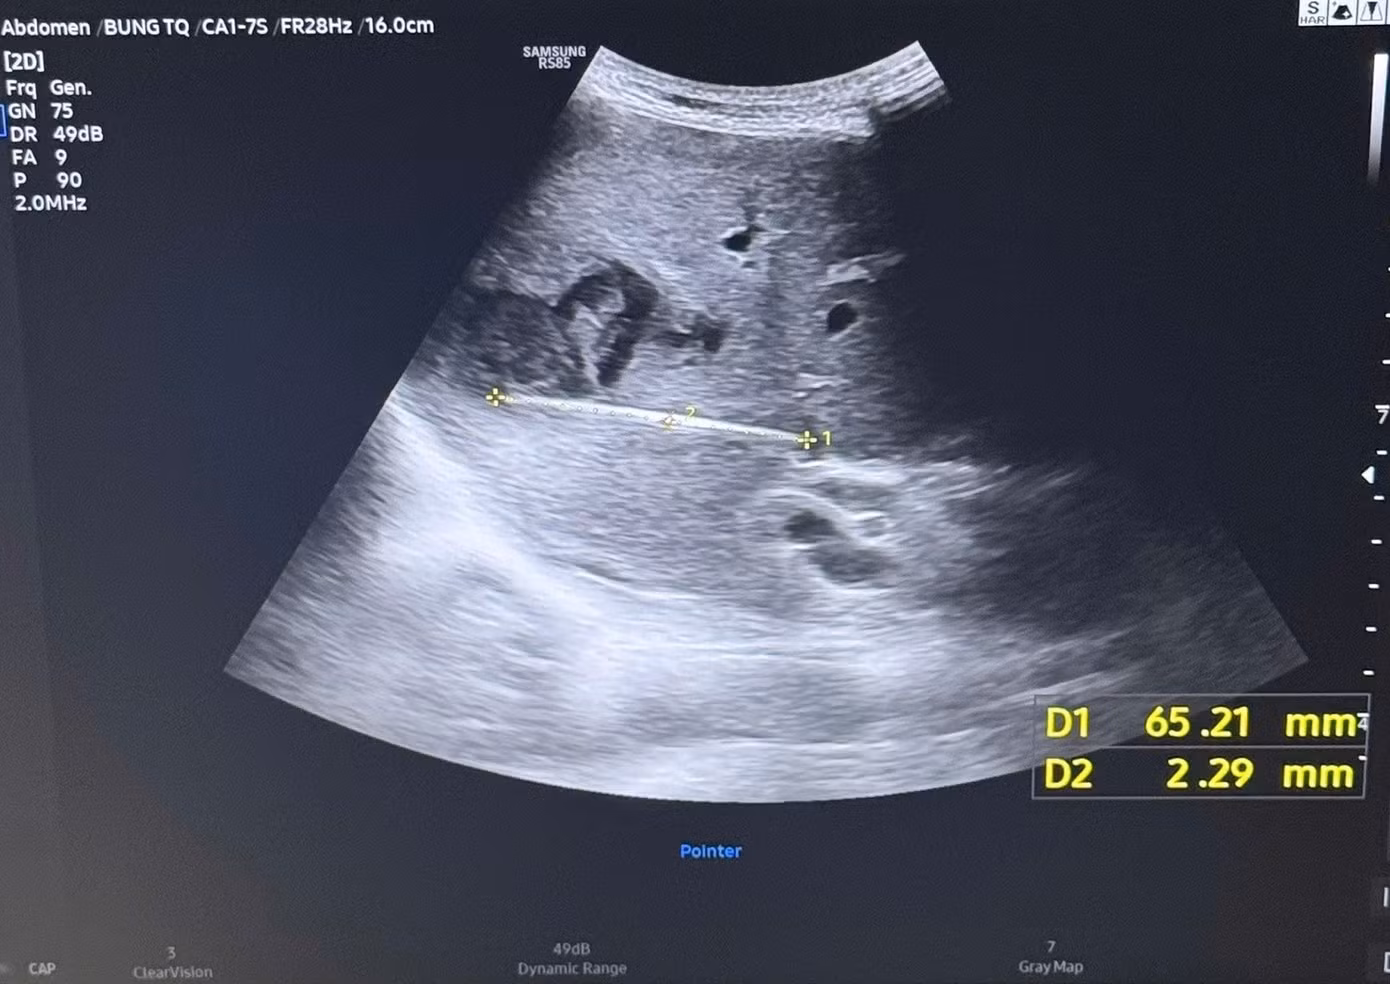

Qua siêu âm kiểm tra và chụp CT ổ bụng, các bác sĩ phát hiện một tổn thương bất thường trong gan với hình ảnh dị vật dài khoảng 7 cm nằm hoàn toàn trong nhu mô gan, kèm theo ổ áp xe sâu.

Hình ảnh kiểm tra phát hiện dị vật xuyên thấu vùng gan của người bệnh gây áp xe nghiêm trọng